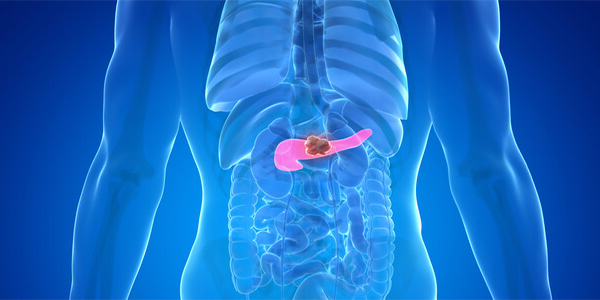

췌장암은 췌장에서 발견되는 암세포로 만들어진 종양이고 우리 몸의 췌장은 보통 15CM 길이가 얇고 긴 모양을 장기중 하나입니다. 췌액 이라고 호출하는 소화액을 분비시켜 십이 지장으로 전달해 주는 역할을 하더라고요.

췌장은 위장의 뒤쪽 몸통의 중앙에 붙어있고 있었고 위, 십이 지장, 소장, 대장 등의 장기에 둘러싸여 있어서 췌장암을 초기 발견하는게 정말 쉽지 않습니다 췌장암의 90% 이상은 췌관의 외분비 세포에 암이 전파되어 선암으로 예사로 췌장암입니다.